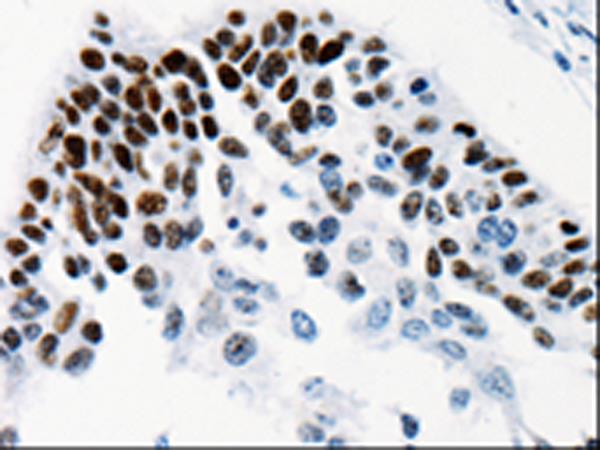

The image is immunohistochemistry of paraffin-embedded Human cervical cancer tissue using (TGIF2LX Antibody) at dilution 1/25. (Original magnification: ×200)